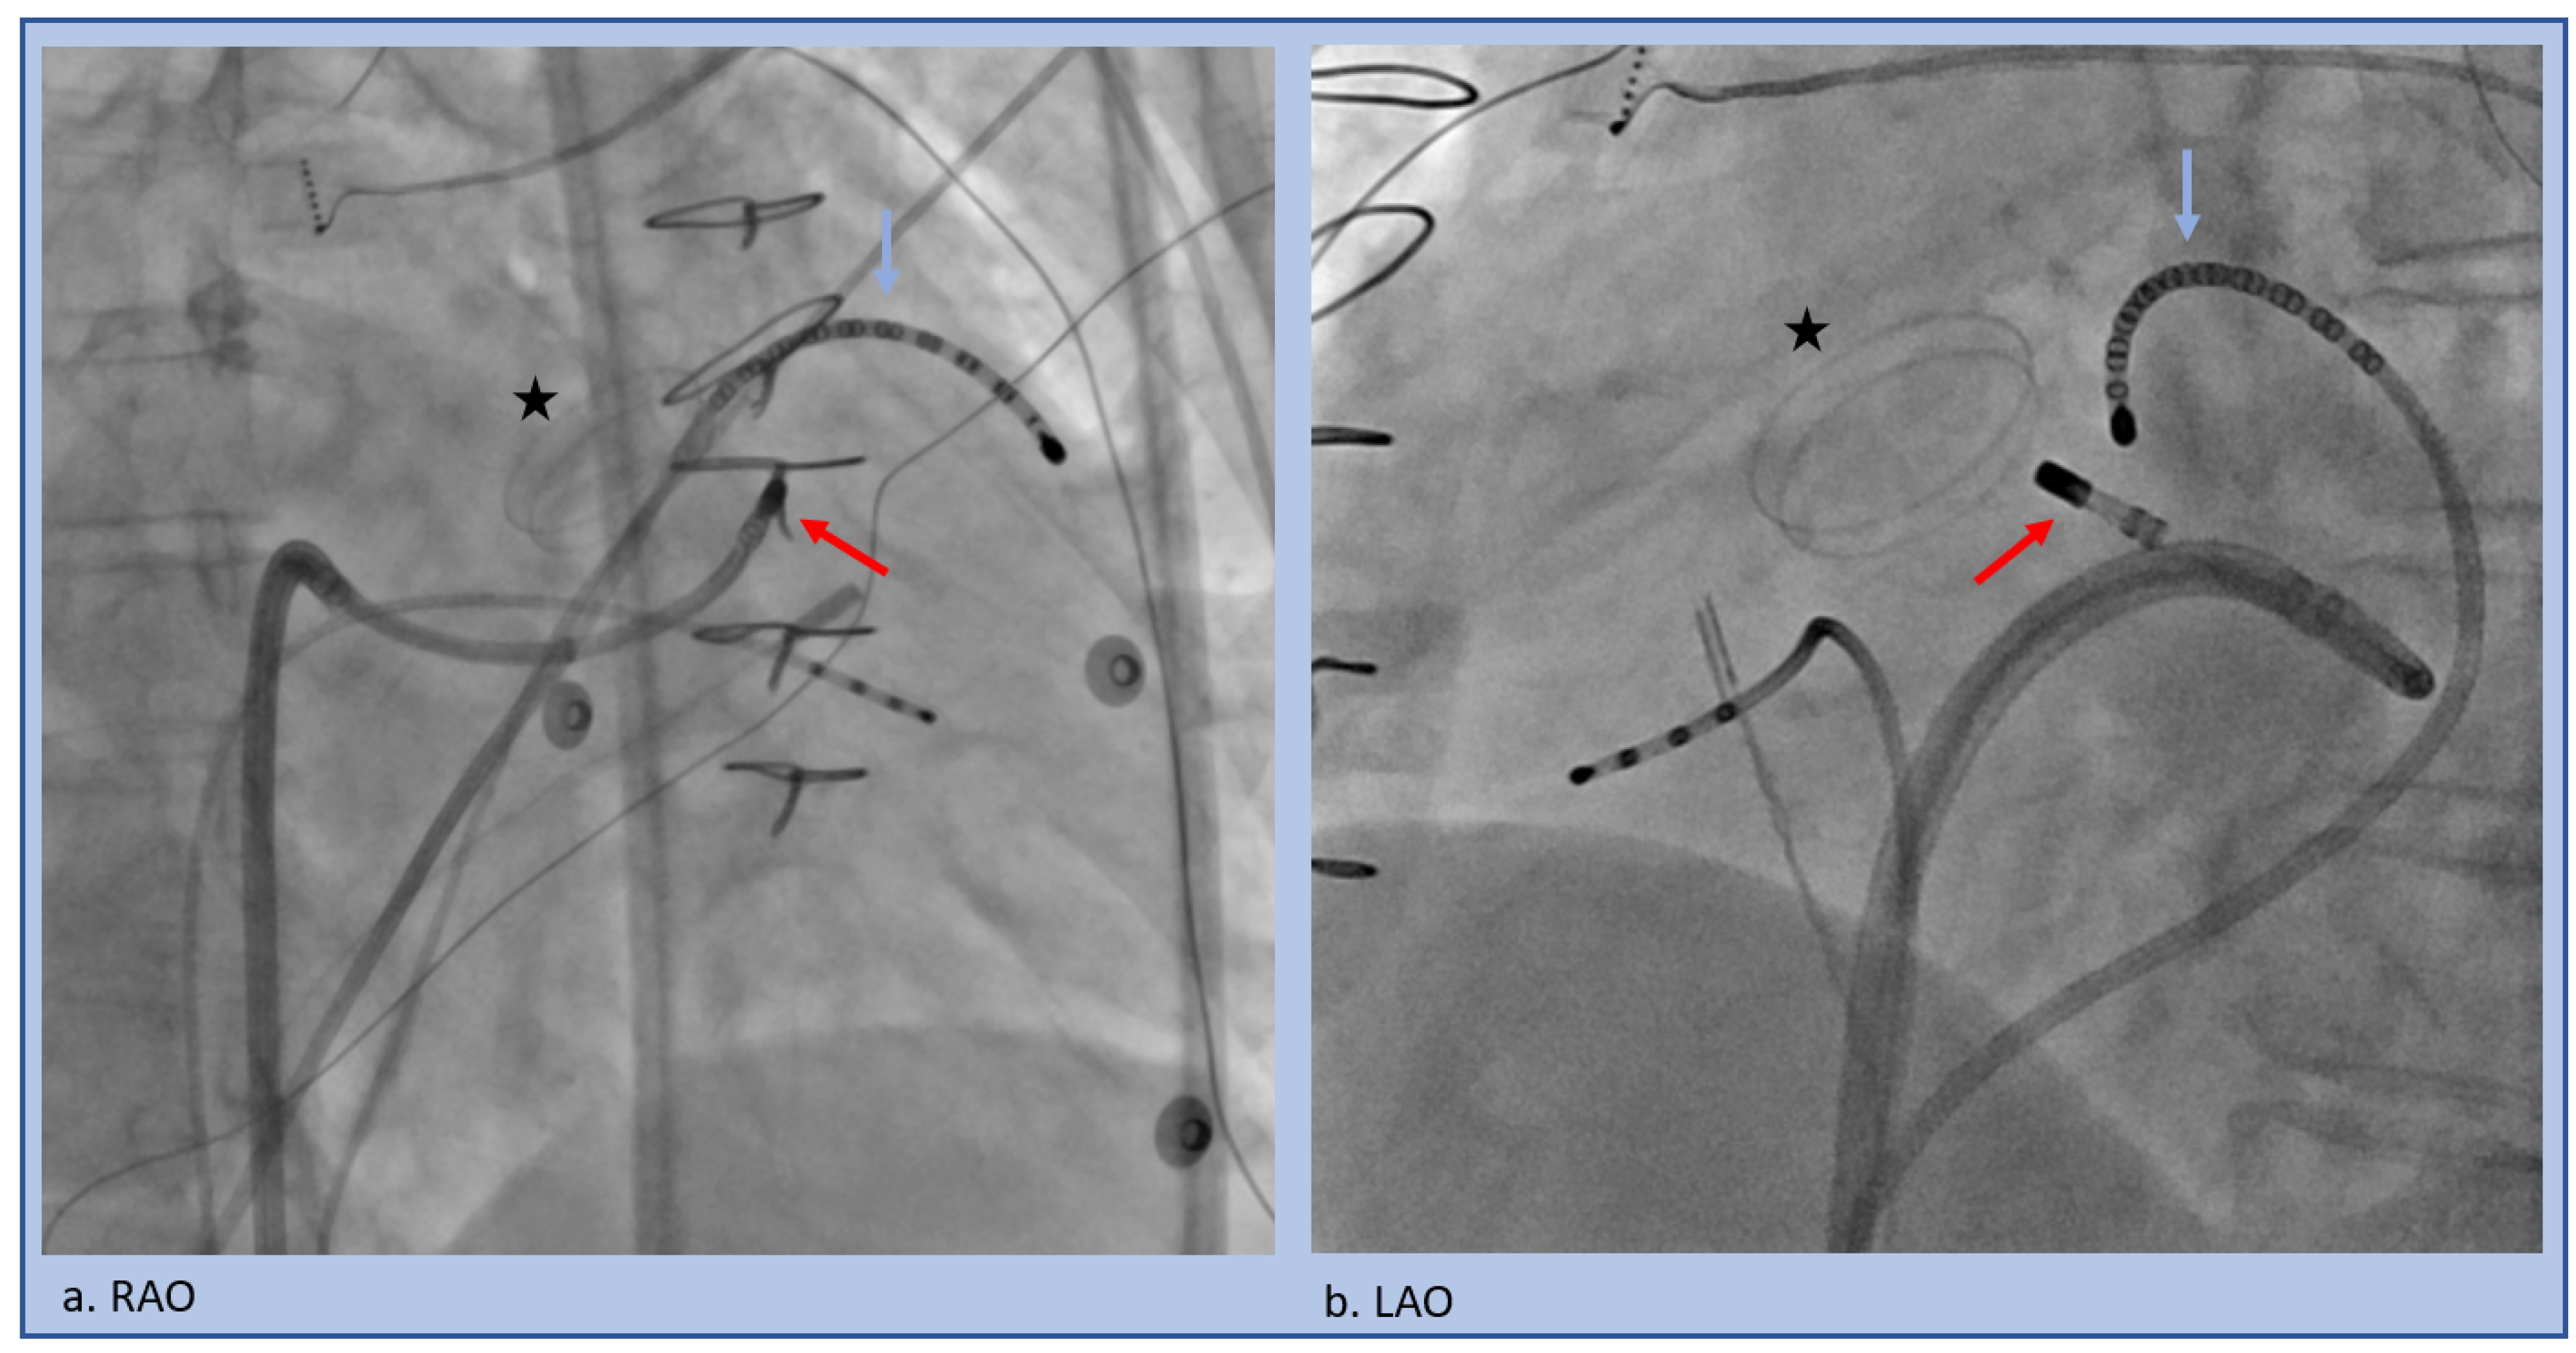

| Moderator Band VT Ablation Tips |

|---|

|